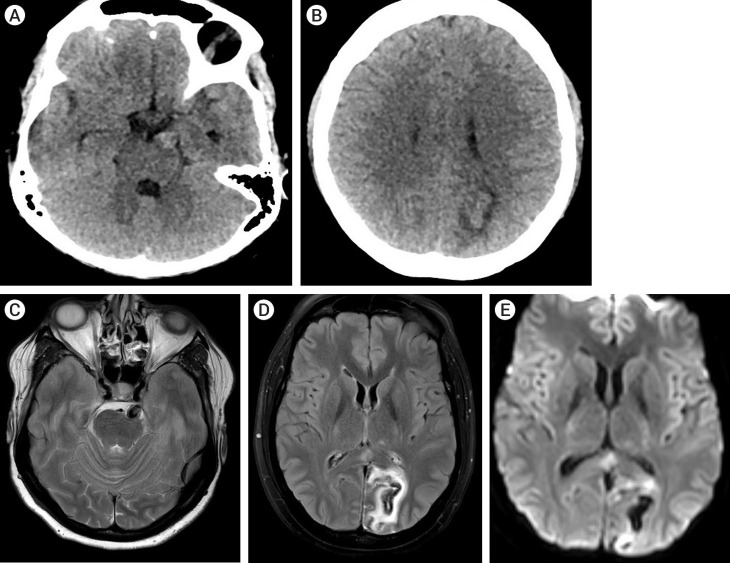

颅神经麻痹可能是颅内动脉瘤的先兆。动脉瘤血管与邻近神经之间存在典型的配对关系,从而导致颅神经病变。孤立的外展神经麻痹可能是未破裂的椎基底动脉循环动脉瘤的局部征兆。据报道,涉及小脑前下动脉(AICA)和小脑后下动脉(PICA)的动脉瘤与外展神经麻痹有关。未破裂动脉瘤的症状是由于邻近神经血管结构的肿块效应造成的。大多数外展神经麻痹在显微外科手术切除后可缓解。在此,我们介绍了一例罕见的未破裂的大脑后动脉(PCA)动脉瘤病例,该病例出现了外展神经麻痹和复视,并伴有对侧偏盲,经血管内线圈栓塞治疗后症状明显改善。

Cranial nerve palsies can be presenting signs of intracranial aneurysms. There is a classic pairing between an aneurysmal vessel and adjacent nerves leading to cranial neuropathy. Isolated abducens nerve palsy can be a localizing sign of an unruptured vertebrobasilar circulation aneurysm. Aneurysms involving Anterior Inferior Cerebellar Artery (AICA) and Posterior Inferior Cerebellar Artery (PICA) have been reported to be associated with abducens nerve palsy. The symptoms in unruptured aneurysms are due to the mass effect on adjacent neurovascular structures. Most of the abducens nerve palsy resolves following microsurgical clipping. Here, we present a rare case of an unruptured Posterior Cerebral Artery (PCA) aneurysm presenting with abducens nerve palsy and diplopia associated with contralateral hemianopsia which markedly improved following endovascular coil embolization.